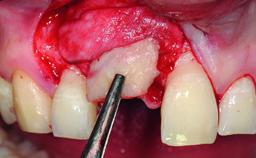

A 32-year-old female Caucasian patient with a compromised maxillary right central incisor was referred to us by a general dentist. Her chief complaints were discomfort and mobility of tooth 11 with unsatisfactory esthetics due to discoloration. The patient reported a previous trauma, some years earlier, as the origin of pathology on the afflicted tooth. Anamnesis was negative for any other dental or periodontal pathology in the remaining dentition. The patient did not take any medication and reported to be a light smoker (5–10 cigs/day). She had high esthetic expectations of her treatment. The extraoral examination revealed a high smile line with full exposure of her maxillary teeth and surrounding soft tissue in the area between the second premolars.

| Bone Augmentation | Horizontal|Simultaneous|Staged |

| Augmentation Materials | Autogenous chips|Xenogenous|Membrane |